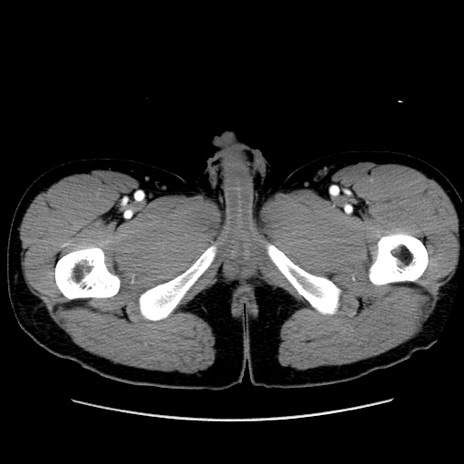

症例36(横断像)

【症例】20歳代 男性

【主訴】心窩部痛

【現病歴】今朝より上腹部痛あり。一旦軽快していたが再度出現したため救急要請。昨日夕に白身の魚を含む刺身を食べた。

【身体所見】BP 136/89mmHg、HR 74/min、BT 37.0℃、腹部:膨満、軟、心窩部に圧痛あり。反跳痛なし、筋性防御なし、腸雑音やや亢進あり。

【データ】WBC 17700、CRP 0.48